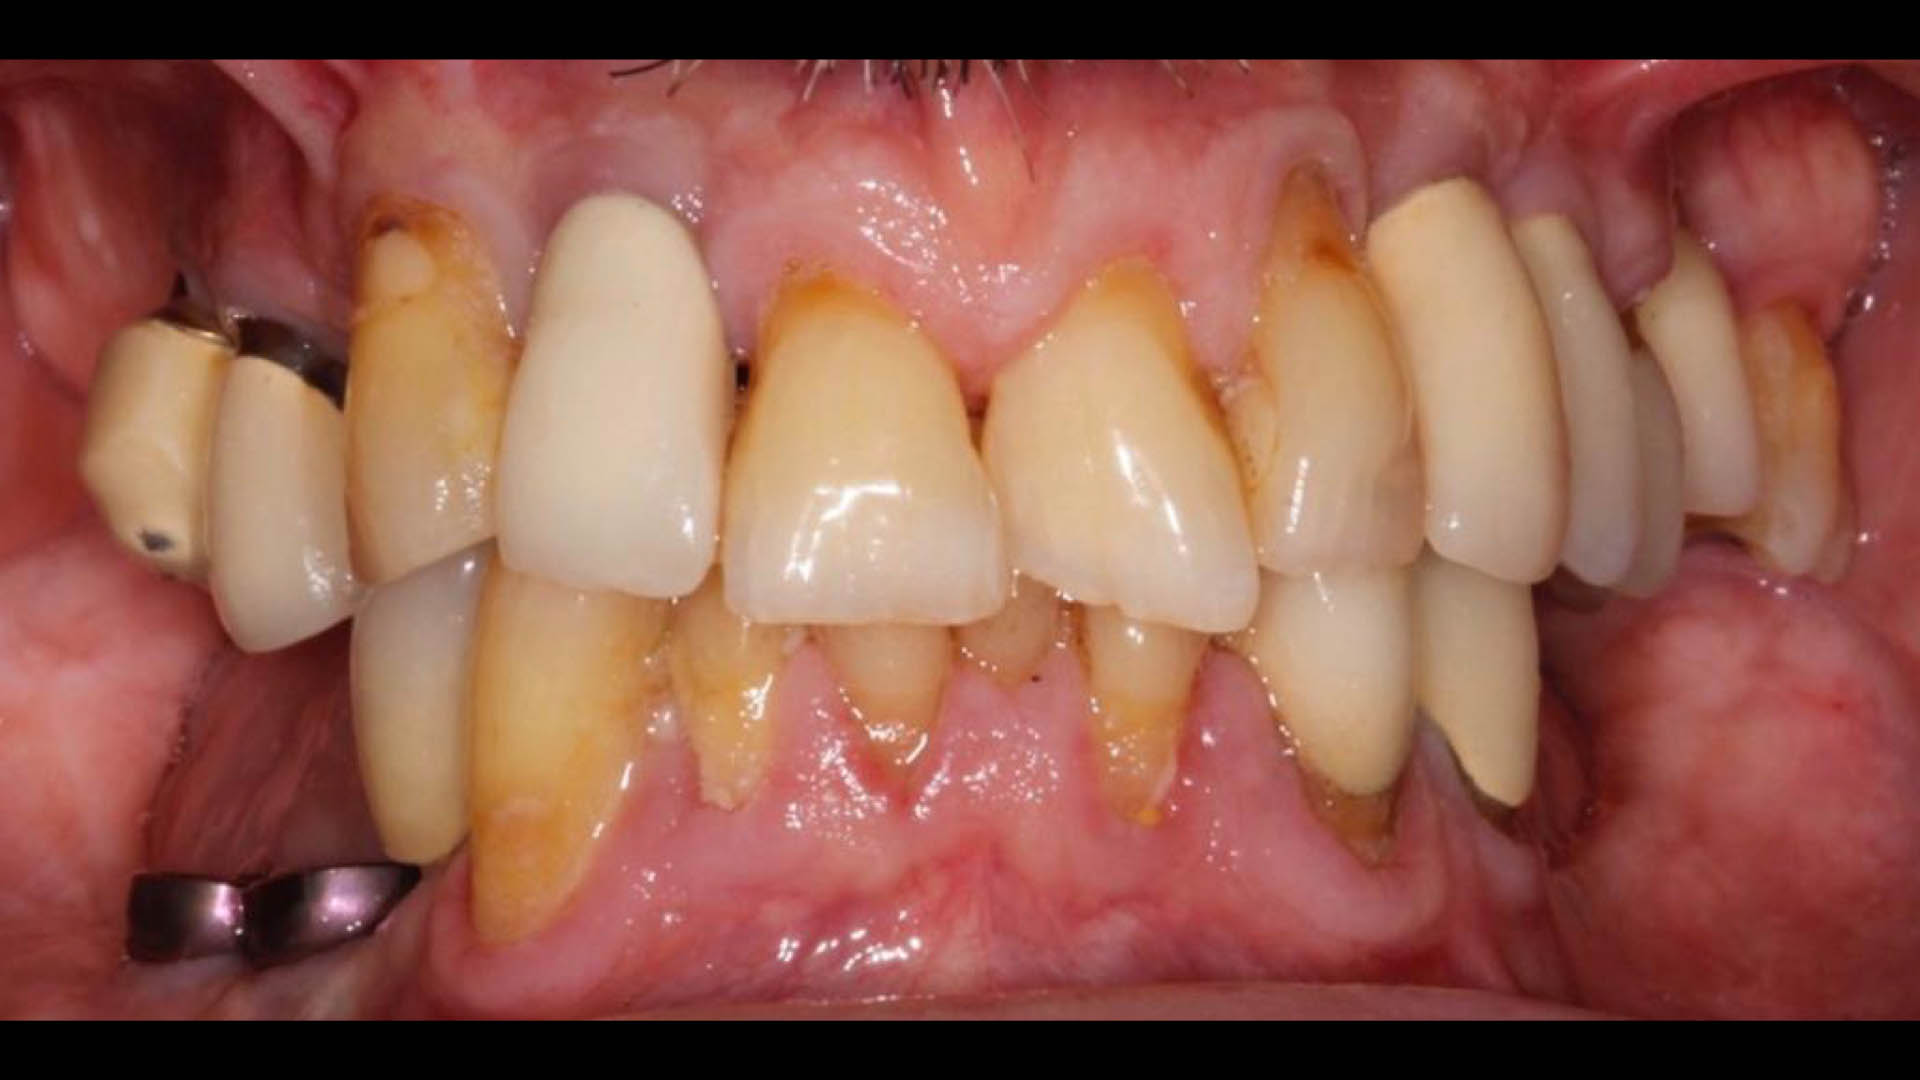

Take a glimpse into the magic of Coral Gables Dentistry through our before and after pictures. See firsthand the incredible smile makeover transformations that have brought confidence and joy to our patients.